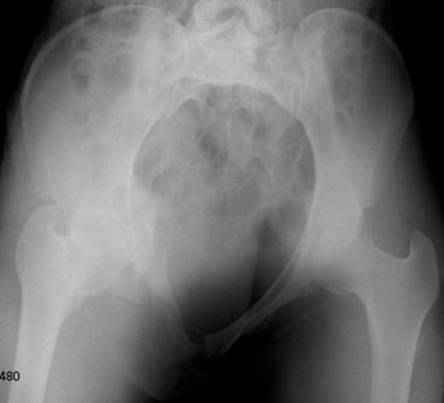

Серия до- и послеоперационных снимков этой пациентки. Хотя бы post factum обсудить. Не знаю, что можно сделать с задними отделами стержневым аппаратом, но три крепких парня открытым путем с помощью "волшебных" слов еле-еле смогли отрепонировать - сзади все было очень ригидно!

Здравствуйте, Евгений! У меня видна только дооперационная проекция inlet.

я бы остановился на передней раме, операция - 30 мин, в таком варианте вроде бы репозиция - ничего, но когда давать нагрузку, ведь в лонном сочленении тоже есть подвижность? а если не давать - зачем операция?